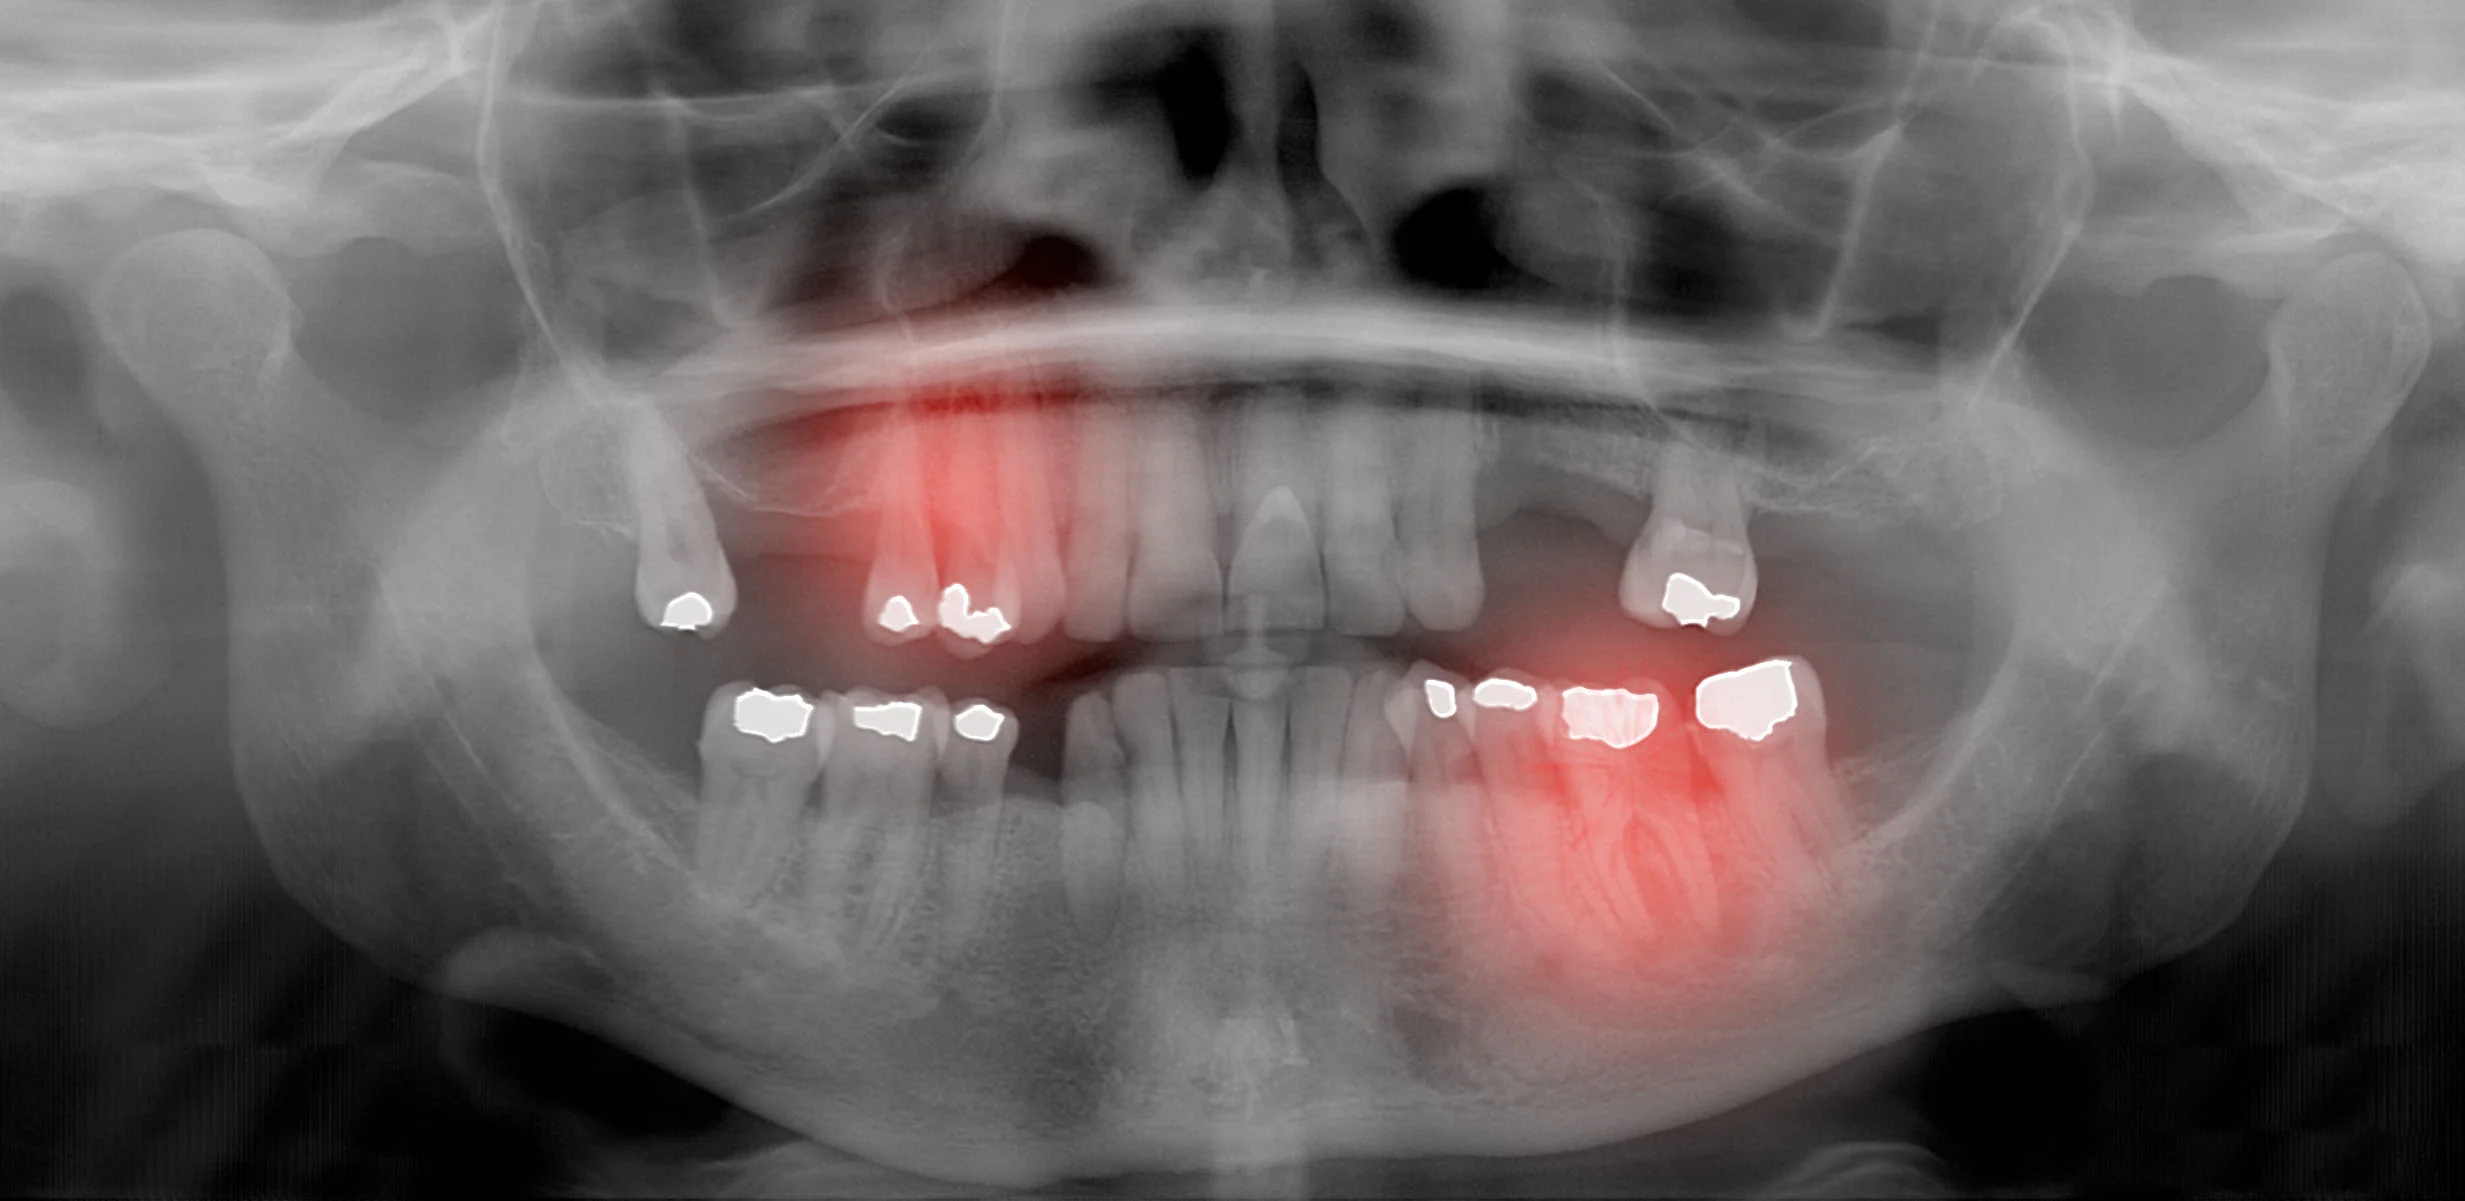

The first symptoms of periodontal disease may not be easy for you to recognize. It isn't too difficult to overlook your bleeding gums and bad breath— especially if you're a smoker — because these symptoms often come and go for long periods of time. But these early warning signs may indicate bigger problems ahead.

Periodontal disease often starts as gingivitis, a bacterial infection that causes inflammation of the gum tissues. If left untreated, this condition can progress to periodontitis, which results in loss of the bone that surrounds the teeth. When bone tissue is lost, the teeth and gums begin to separate, forming pockets that provide an ideal environment for bacteria to thrive. Ultimately, the disease may cause tooth loss, painful abscesses, and even systemic inflammation.

perioproblem.jpg

Brushing and flossing daily, and having regular professional cleanings are the best way to prevent periodontal disease. If it does develop, a number of treatments are available. Evaluating your oral hygiene techniques and seeking to improve them is a first step at control. Your dentist can also remove plaque and tartar with special tools, in the cleaning technique called “root planing” or “root debridement.” In some cases, periodontal surgery may be necessary.